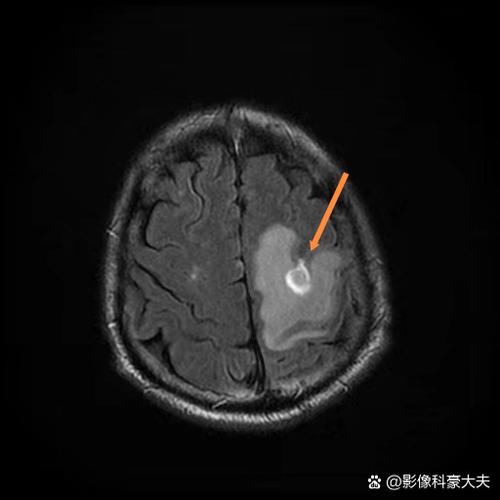

(图片来源网络,侵删)- 核磁: 可以在发病后30分钟到1小时内就发现脑梗死的迹象,它对早期细胞内的水分变化非常敏感,一旦脑细胞开始缺血坏死,DWI序列上就会显示出高信号(亮点)。

- 核磁: 对非常小的梗死灶、位于脑干、小脑等后颅窝的病灶,显示得非常清楚,轻微脑梗往往病灶很小,CT很容易漏诊。